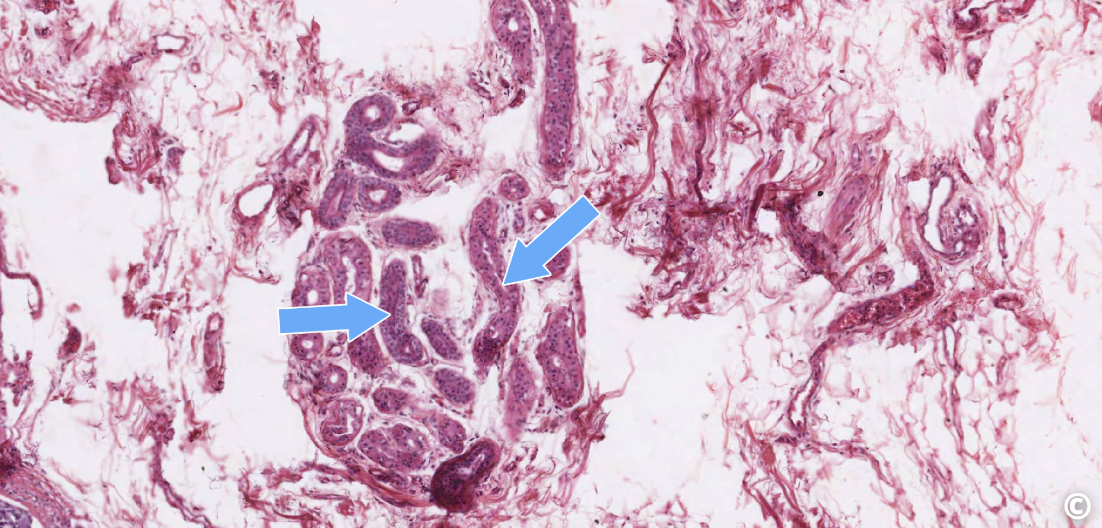

<p>identify area of histological slide, type of CT, and identify structures</p>

identify area of histological slide, type of CT, and identify structures

epidermis, loose CT, lamina propria